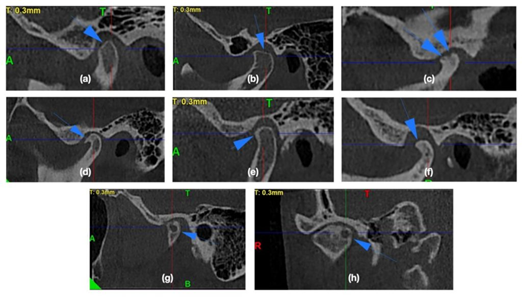

| - CBCT trong chẩn đoán bệnh lý khớp thái dương hàm: Phim CBCT trực quan chụp khớp thái dương hàm (TMJ) mỗi bên có thể sử dụng để đánh giá cho những thay đổi của phần xương vùng này đến lồi cầu xương hàm dưới và xương thái dương cũng như tương quan lổi cầu trong hõm khớp. Những thay đổi của phần xương này có thể là kết quả của chấn thương/gãy xương, loạn sản, quá sản hay các bệnh lý về xương | | |